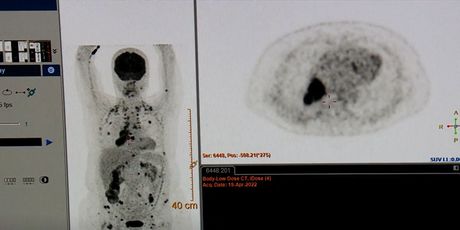

Personalizirano liječenjeFoto: DNEVNIK.hr

Hrvatski onkološki pacijenti već bi se 2024. trebali liječiti po konceptu personalizirane medicine. U Zagrebu su u ponedjeljak potpisani ugovori o izgradnji Centra za liječenja malignih bolesti u Zaboku.

Prava terapija za pravog pacijenta u pravo vrijeme. Tako bi se trebali liječiti pacijenti u Centru za liječenje malignih bolesti.